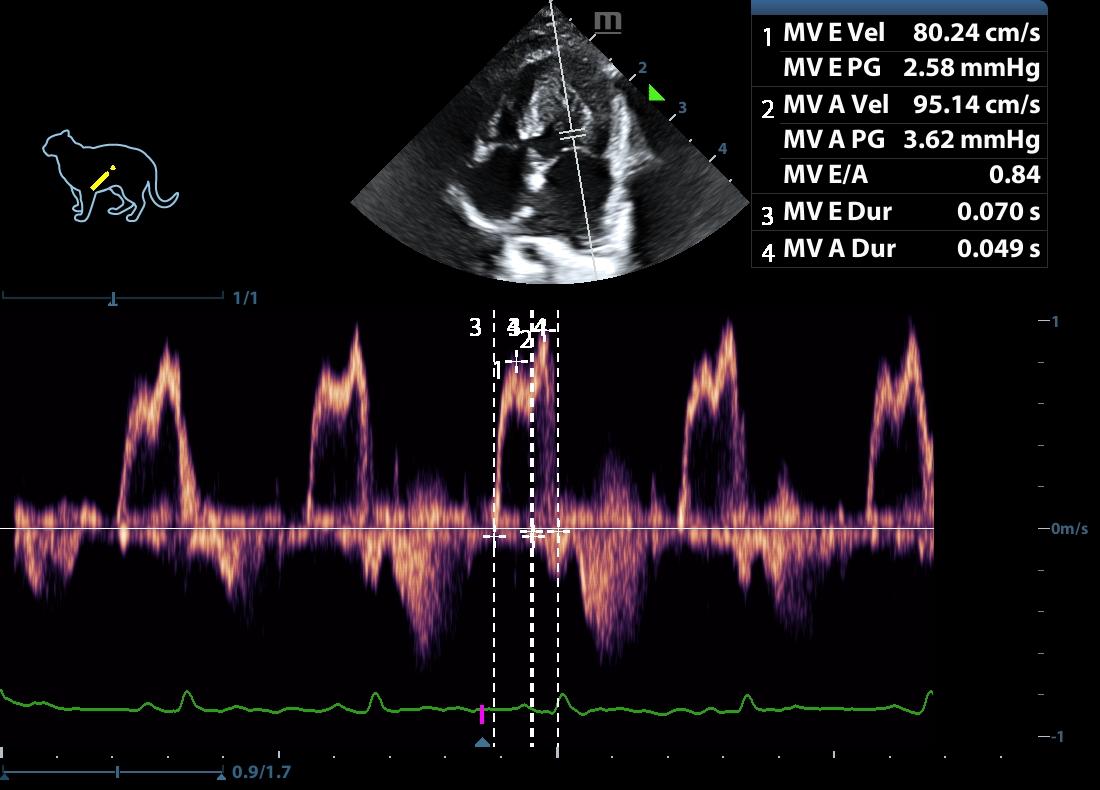

202505170048360153CARD.JPG